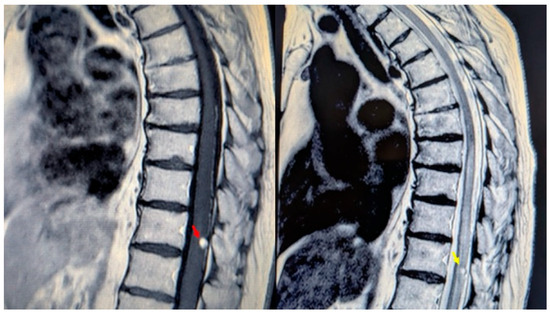

A 76-year-old woman presented with a six-month history of progressive dorso-lumbar pain. Neurological examination revealed significant pain but preserved lower limb strength; bladder dysfunction was present and worsening overtime with a sub-acute trend in the hours before surgery. Magnetic resonance imaging (MRI) of the thoracic spine revealed an expansive lesion at the T11 vertebral level [Figure 1]. Preoperative spinal angiography was not performed, as the imaging findings were interpreted as consistent with a hemangioma without clear evidence of flow voids or abnormal vascular connections. The patient’s medical history included long QT syndrome, osteoporosis, and bilateral carpal tunnel syndrome. Neurosurgical evaluation indicated the need for timely surgical resection due to the ongoing worsening of symptoms and to the unclear imaging.

Figure 1.

MRI of the thoracic spine. Left: T1-weighted image showing the expansive lesion at the T11 level (red arrow). Right: T2-weighted image revealing the lesion with surrounding edema (yellow arrow).